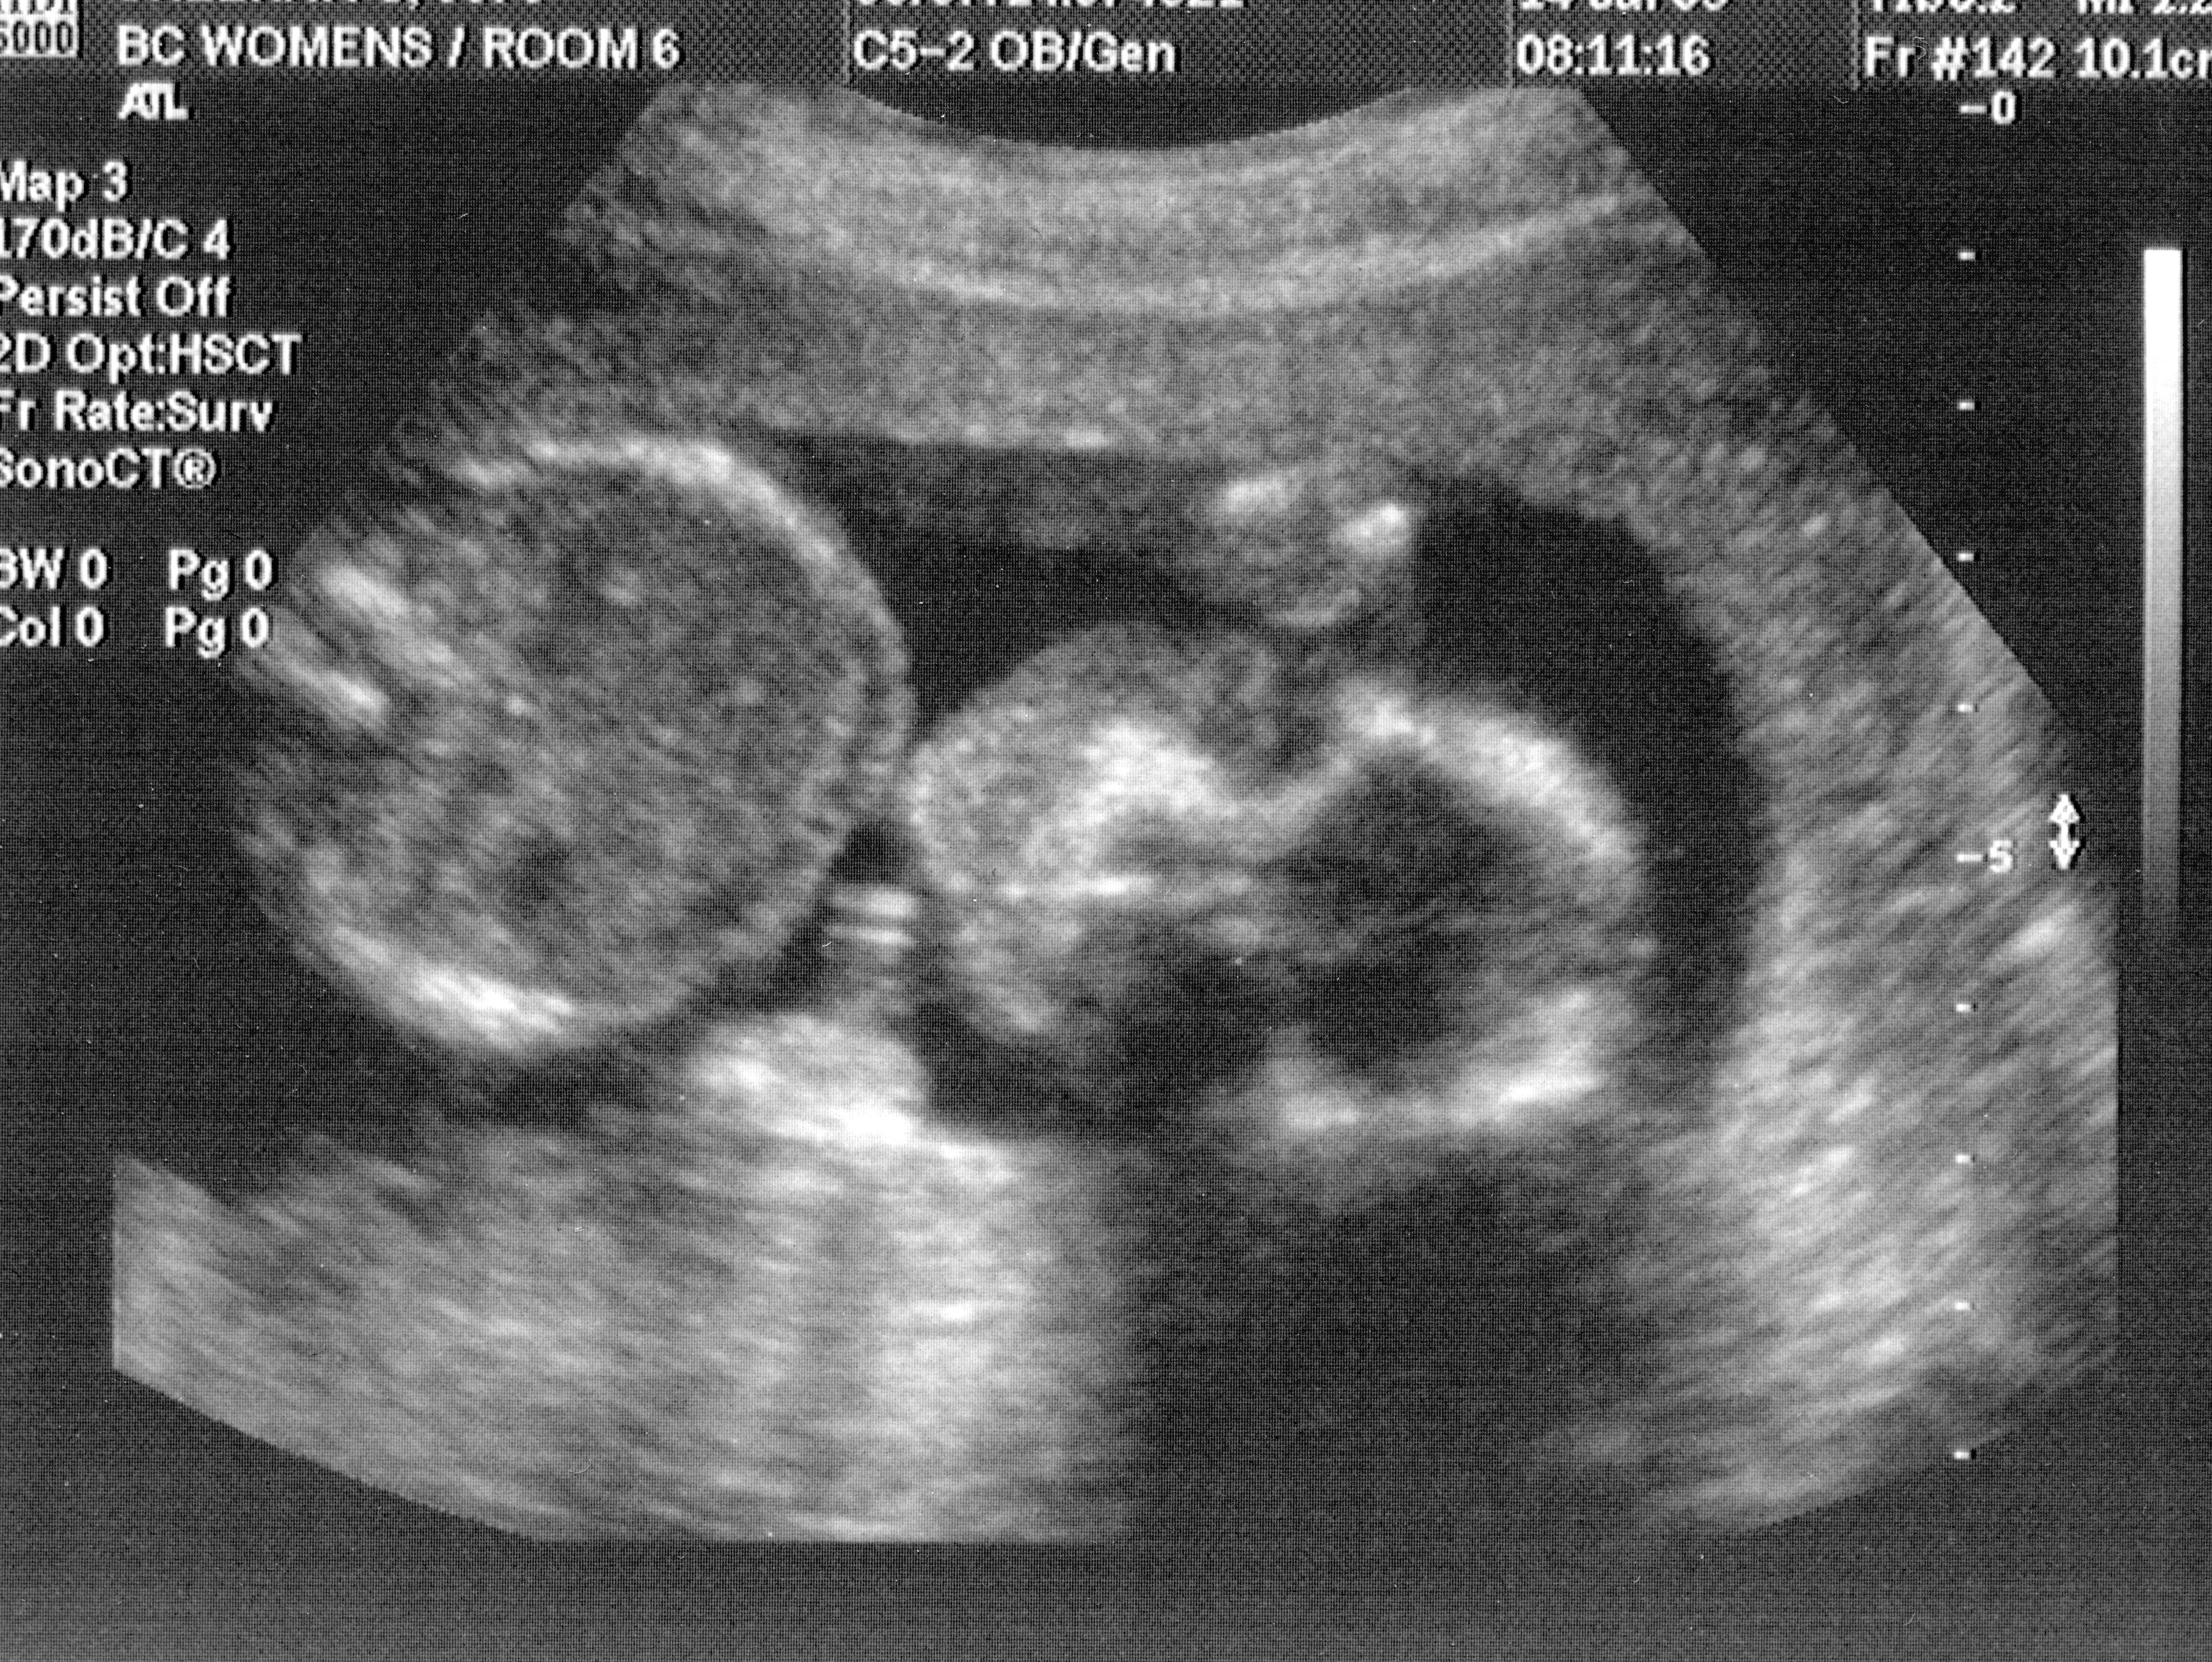

FAS is present in an estimated 0.02-0.15% of live births, affecting growth, facial and cranial features, structural, neurological, and intellectual development. FAS children exhibit learning difficulties, low impulse control, and an array of cognitive and motor-skill challenges—rendered all the more tragic given the preventability of the condition.